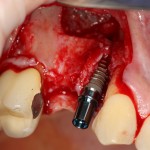

Затем устанавливаем имплантат. В данном случае, Friadent XiVE. Диаметром 3,4 мм — это минимальный размер импланта, который можно использовать в эстетически значимой зоне:

Не обращаем внимания ни на стабильность импланта, ни на объемы окружающей костной ткани. Имплантат после установки может крутиться, шататься и вращаться — правило, когда первичная стабильность была главным условием успешной имплантации, применимо лишь ко второму этапу развития имплантологии. Более того, друзья, есть импланты, которые вообще не предполагают первичной стабильности. Например, Bicon.

Очень хочется использовать имплантат поменьше диаметром (3.0 мм), но, как я уже отметил, минимальный размер в эстетически значимой зоне — 3,4 мм. Связано это с тем, что на импланты диаметром 3.0 мм выпускается очень небольшое количество супраструктур (абатментов), поэтому в дальнейшем можно столкнуться со сложностями при протезировании.

После установки второго импланта в правильное положение (ориентируемся по оси и форме лунки зуба), внешнюю кортикальную стенку восстанавливаем костным фрагментом, получившимся после синуслифтинга:

На деле — ничего сложного. Костный фрагмент просто фиксируется одним винтом. Таким образом восстанавливается отсутствующая костная стенка.